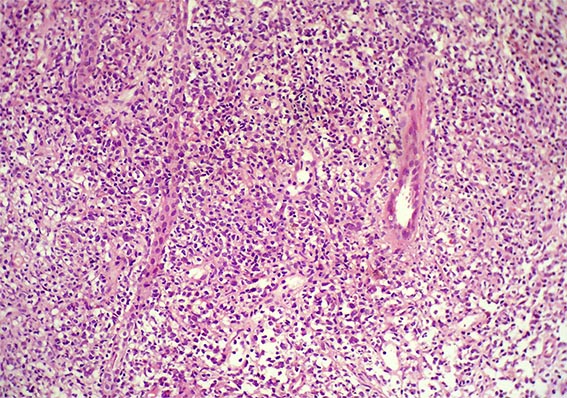

The patient is a 41-year-old woman with constitutional symptoms. Among the many studies undertaken to determine its cause, pyuria and microscopic hematuria were found in the urinary sediment, and, by ultrasonography, a ill-defined mass was evidenced on the renal upper pole of the left kidney.

A biopsy of the mass was obtained. See the images.

Figure 1. H&E, X200.